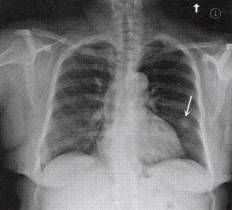

一、X线表现

顾名思义,爆米花样钙化征指病灶内钙化呈爆米花样改变,常见于错构瘤,是错构瘤的 特征性改变。错构瘤的胸部X线表现多样:①肺野内边缘清楚的圆形、卵团形孤立结节阴 影,直径大多<3cm;②部分病变有浅分叶状、切迹,多数密度均匀。少数病变内有斑点状 钙化影,典型者呈“爆米花”样钙化。见图1。

图1爆米花样钙化征:左中下肺野可见边缘规则的球形病灶,其内可见钙化灶